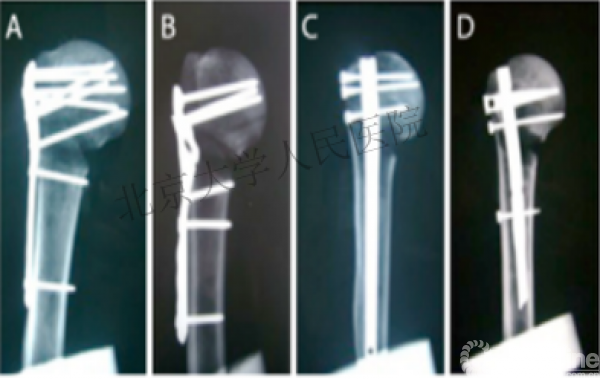

复位良好的标准:颈干角:135°,大结节与肱骨头距离:8mm

术后3月随访:继发性颈干角变小22°(5-82),肱骨头内翻,达46%

严重影响了患者的生活质量